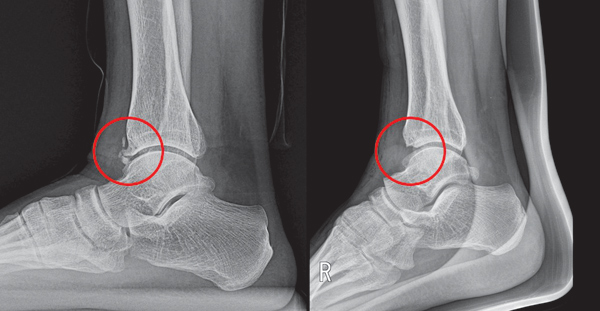

스트레스성 골절

운동량이 급격히 증가하거나 체중이 늘었을 때, 발의 뼈에 미세한 균열이 생길 수 있습니다. 발바닥 중간 부분이나 앞꿈치에서 지속적인 통증이 나타나며, 휴식 시에도 통증이 사라지지 않는 특징이 있습니다.